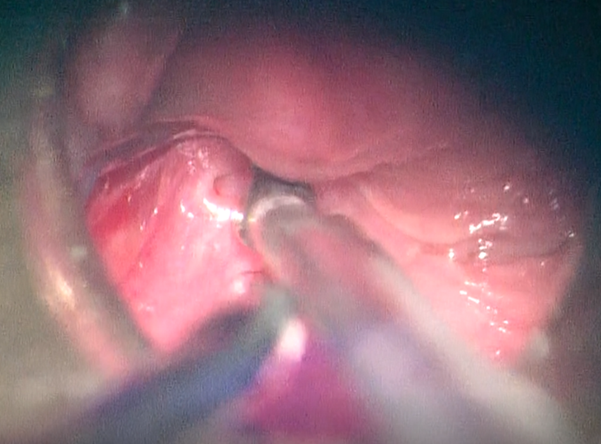

Vasalva’s maneuver. Patient underwent hypopharyngoscopy revealing the presence

of an orifice of the sinus was found in the left piriform fossa (Figure 1).

Figure

1. Orifice of the fistula in the left

piriform fossa in endoscopic view.